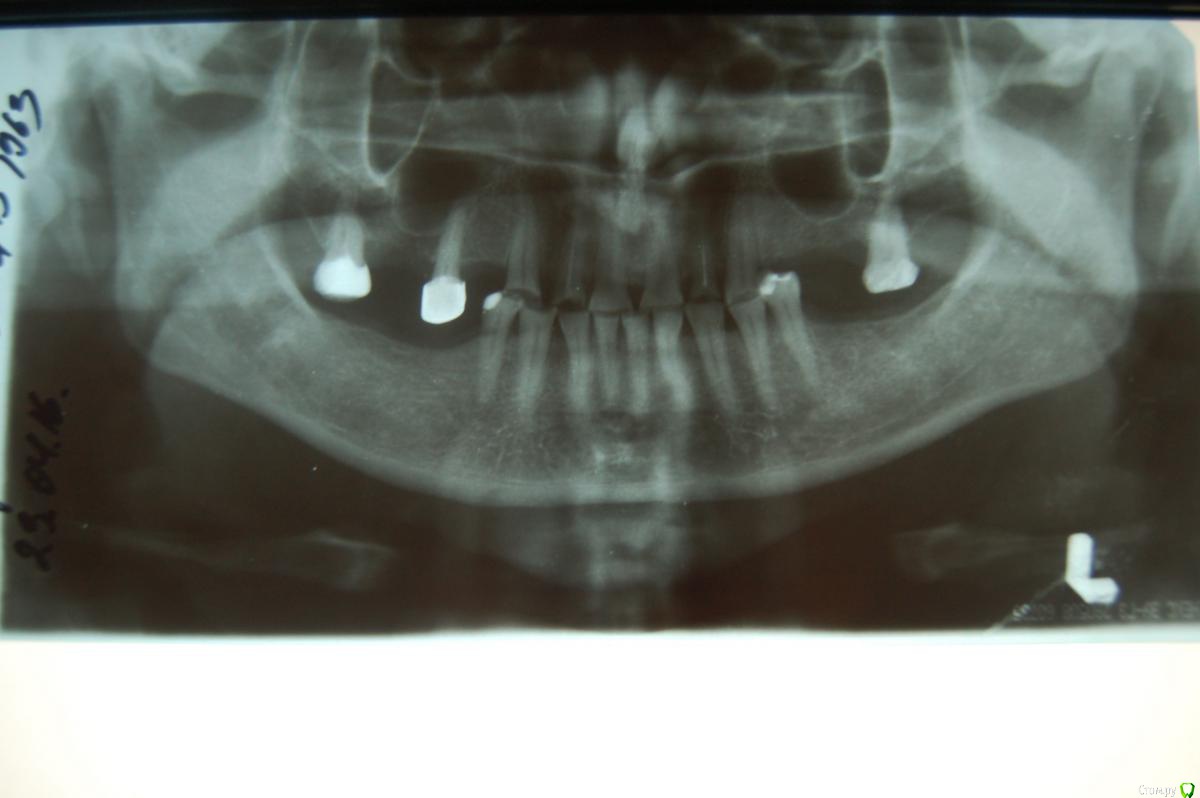

Пациентка(1963 г.р.) обратилась с желанием сделать зубы до декабря(свадьба сына). Говорит, что у нее, что то случилось с опорно-двигательной системой и зубы стерлись за год. Сжимание и скрежетание зубами отрицает. Финансово ограничена. Согласна по цене на цельнолитые, цельнолитые с керамической облицовкой вестибулярно, бюгельный кламмерный протез на нч. Возможно согласится на металлокерамику на часть зубов, временные пластмассовые коронки.

Ортопантомограмма(04.2016). На данный момент 12 зуб удален, запломбированы каналы в большинстве зубов.